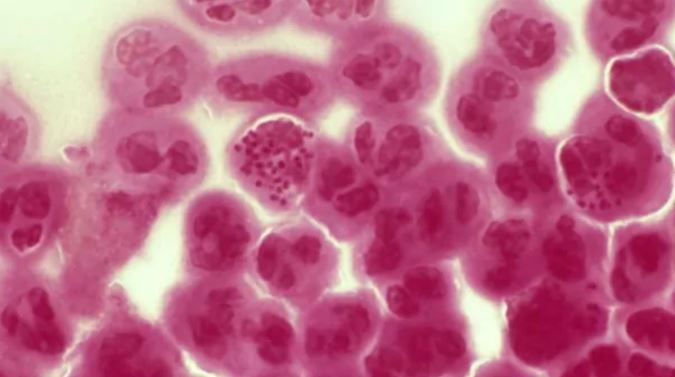

Advierten de una inminente propagación de gonorrea

Los nuevos cepos serían resistentes a los antibióticos.

A lo menos tres personas en el mundo están infectadas con cepas de gonorrea totalmente intratables que es probable que se propaguen a otros a través del sexo, dijo el viernes la Organización Mundial de la Salud (OMS).